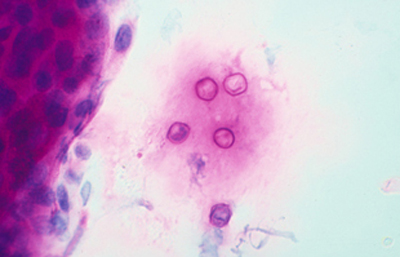

Las coloraciones empleadas en extendidos corneales para visualizar los quistes y trofozoitos de Acanthamoebas usando métodos sencillos son múltiples, siendo las que nos parecen más recomendables las coloraciones de Giemsa y el Acido Periódico de Schiff (PAS), (Figura 33 y 34) ambas usuales en los laboratorios de patología.

Fig. 33 PAS, Original x250

Fig. 34 PAS, Original x160